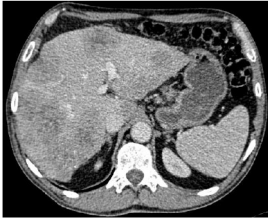

En la re estadificación a los 6 meses se evidenció por TC disminución de tamaño de lesiones hepáticas, presentando necrosis y calcificaciones de mayor grado con respecto a estudios previos, sin nuevas lesiones hepáticas a distancia, ni adenomegalias (Fig. 1a). Se complementó la valoración con resonancia nuclear magnética (RNM) y tomografía por emisión de positrones (PET TC) (estudios no realizados inicialmente) los cuales no evidenciaron enfermedad extrahepática ni diferencias significativas respecto a hallazgos de TC. Se destaca descenso de marcadores tumorales pre y post quimioterapia de conversión (CEA 281 a 2.55 ng/ml y CA19-9 de 125 a 18.62 U/ml respectivamente, sabiendo que los valores normales son CEA: menor o igual a 4 U/ml y CA19-9: 27 U/ml).